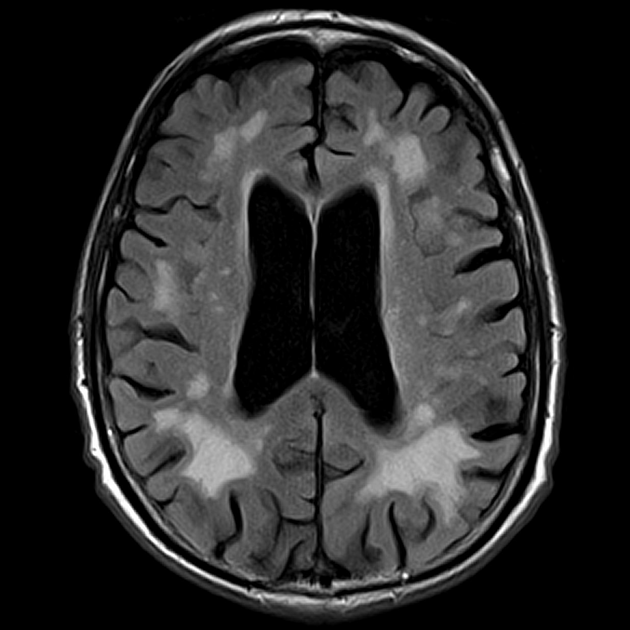

Выглядит это так.

Видите эти белые очаговые изменения вокруг черных желудочков? Это и есть лейкоареоз, но тут очень выраженный. Fazekas 3.

Из-за разобщения связей мозга с мозжечком - возникает шаткость, головокружение. Из-за нарушения связей с зонами контроля движений - скованность, тремор, а если изменения касаются гиппокампа, то страдает память.